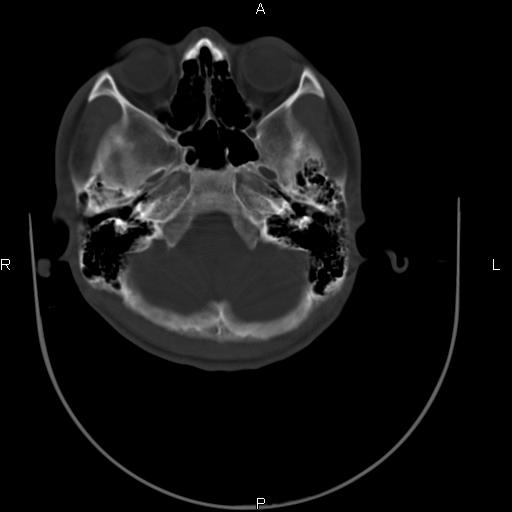

标题: CT27115:大家看一看,这孩子的颅骨表现? [打印本页]

标题: CT27115:大家看一看,这孩子的颅骨表现?

两名中学生打架,脑质内未见异常,未上传。

颅骨未见骨折征象。

两例——颅骨结构正常,未见明显骨折征象。